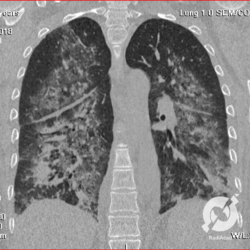

Lesões intersticiais reticulares difusas, aumento do volume cardíaco (Rx)/Opacidades em vidro fosco, espessamento septal e consolidações alveolares difusas, com predomínio peri-hilar bilateral. Edema agudo de pulmão.